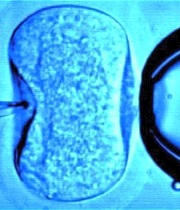

El investigador británico Robert G. Edwards es el ganador del Premio Nobel de Medicina 2010 por sus investigaciones sobre la fecundación in vitro, comunicó el Instituto Karolinska de Estocolmo.

E

dwards, "padre" del primer bebé probeta, la británica Louise Brown (1978), comenzó sus investigaciones sobre la fecundación in vitro a mediados de la década de 1950, planteando la posibilidad de extraer un óvulo, fecundarlo con esperma en un laboratorio y volver a introducirlo posteriormente en el cuerpo de la mujer.